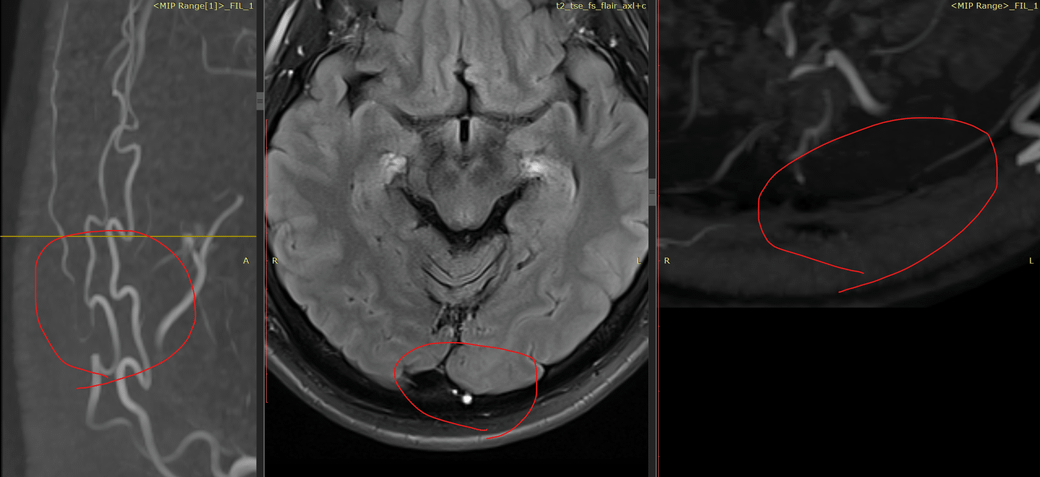

MRA 판독 부탁드립니다. 정상 맞나요?

mri mra 정상 소견 받았는데 제가 찾아보니 이상한 부분이 있어서요.

위 세 사진은 같은 부위입니다.

1. mra

2. t2 flair

3. mra

셋 모두 조영제를 사용한 영상입니다.

특별한 이상소견이 보이지 않는 MRA 사진입니다.

3장의 컷만으로는 확실한 감별이 어렵기도 합니다.